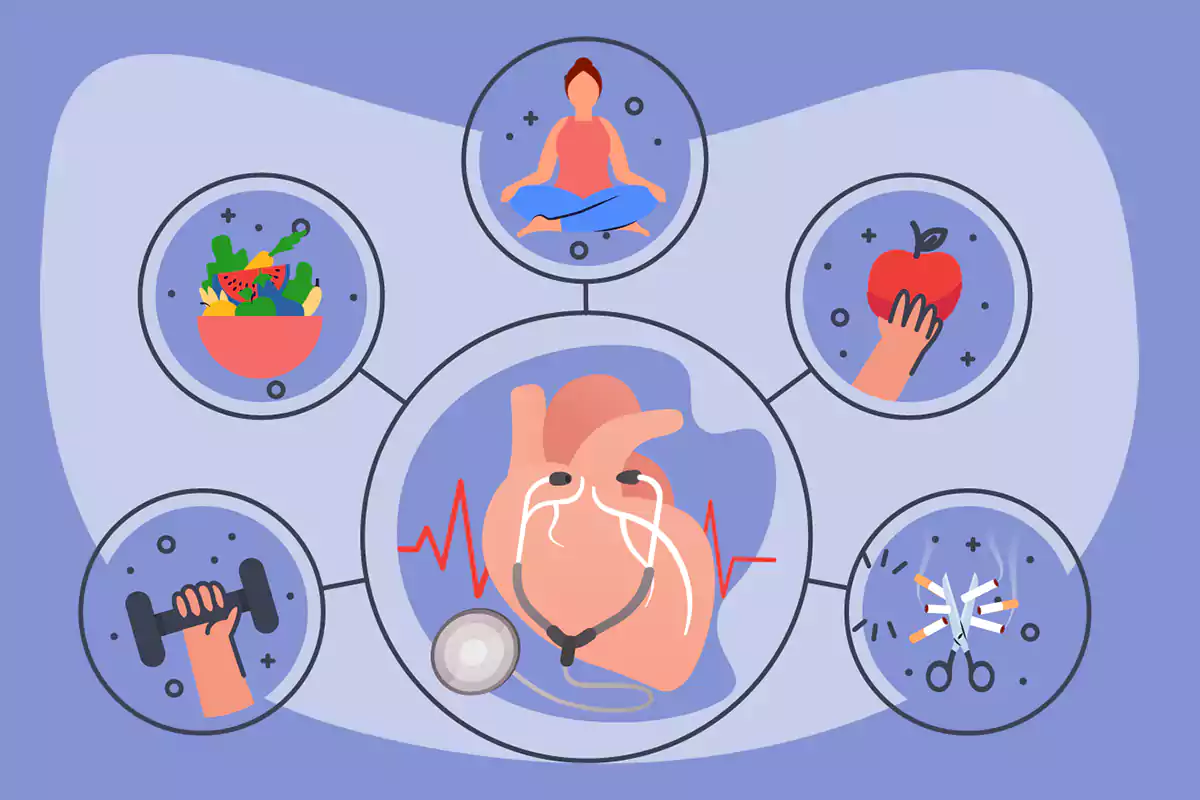

روشهای داشتن یک سبک زندگی برای سلامت قلب

1) پرهیز از دخانیات

یسیگار یکی از مهمترین عوامل خطر ابتلا به حمله قلبی در سنین جوانی است و ترک آن میتواند به شدت سلامت قلب را بهبود بخشد. اگر هم اکنون سیگار میکشید، ترک آن هرچه زودتر میتواند سلامت قلب و سیستم گردش خون شما را بهبود بخشد.

2) کاهش کلسترول

3) کنترل دیابت

4)کنترل فشار خون

حفظ بهداشت دهان و دندان

چرا خواب کافی اهمیت دارد؟

مدیریت سلامت روان و استرس

پایه و اساس سلامت عمومی، داشتن قلبی سالم است. در هر سنی میتوان با اتخاذ یک سبک زندگی سالم، از بیماریهای قلبی پیشگیری کرده و خطر حمله قلبی یا سکته مغزی را کاهش داد. شما میتوانید در هر سنی حفظ سلامت قلب خود را آغاز کنید. واقعیت این است که هرچه زودتر تصمیمهای سالمتری بگیرید، مدت بیشتری از مزایای آن برخوردار خواهید شد. اما حتی اگر قبلاً دچار حمله قلبی و درد قفسه سینه شدهاید، جایگزین کردن عادتهای ناسالم با رفتارهای سالم میتواند به بهبود و حمایت از سلامتی کمک کند.

ورزش کردن و مصرف غذاهای سالمتر از بهترین راهکارها برای تقویت سلامت قلب هستند.